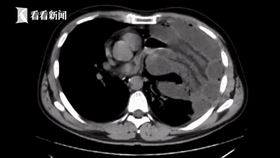

胸腔塞滿「2米小腸」 醫一看也驚呆

中國廣東省佛山市一名男子平常喜歡健身運動,也經常豪飲...